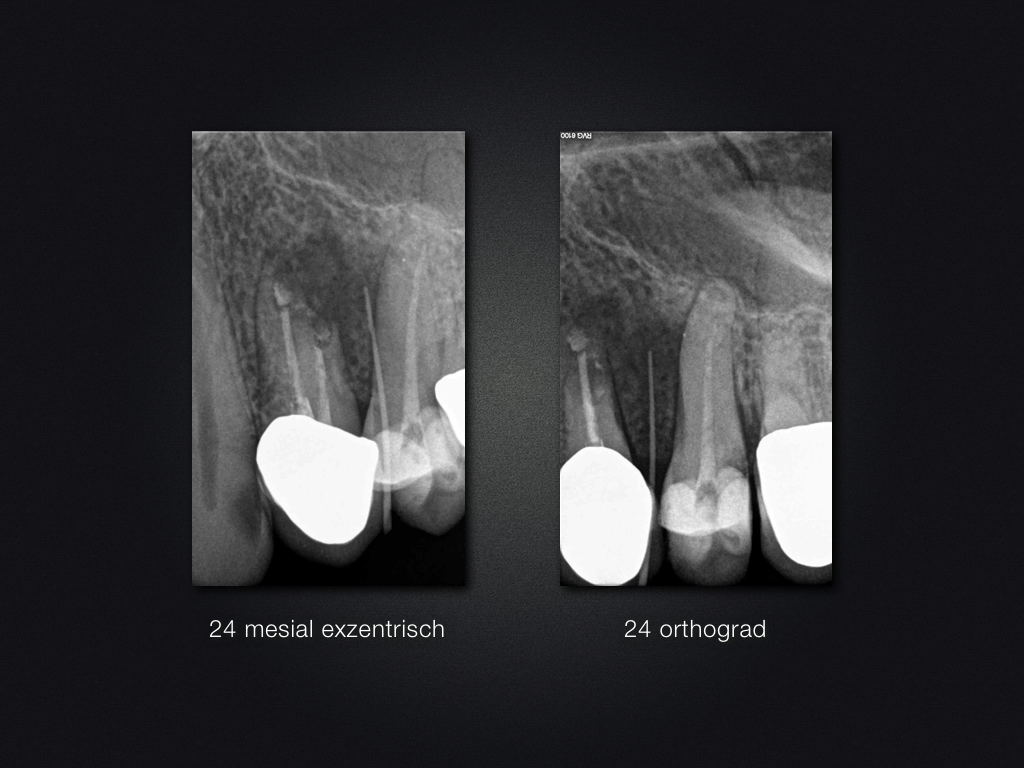

24D.004

Ohne Erfolg …